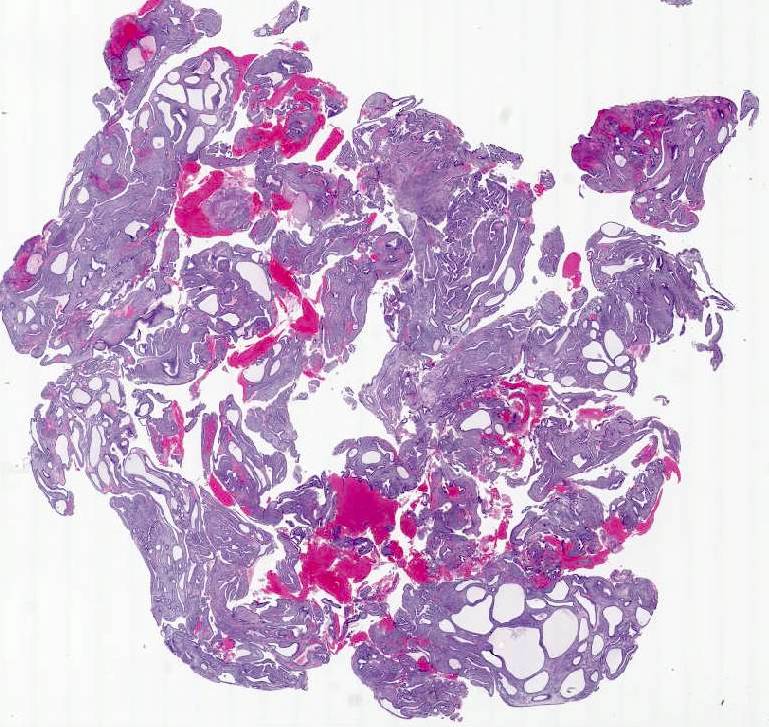

Microscopic (histologic) images

A 45 year old woman, who has been treated with Lupron for longstanding endometriosis and fibroids, underwent total hysterectomy. Most leiomyomas showed morphologic changes depicted in this figure. What additional features would be required to diagnose treatment related degenerative changes?